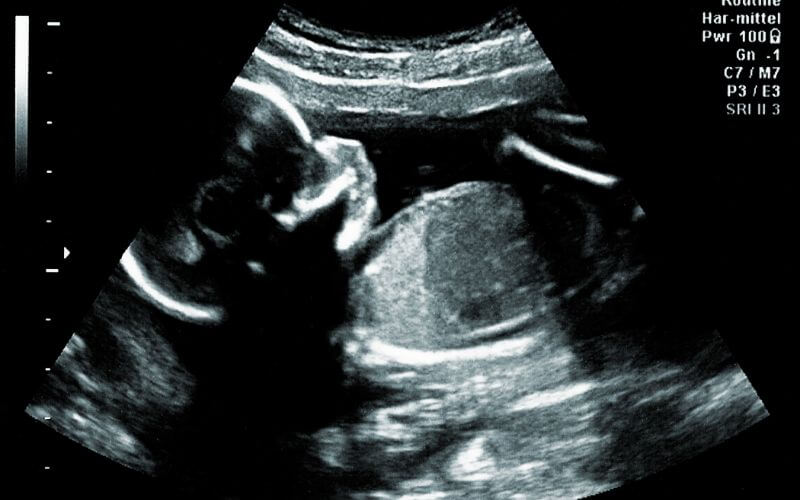

À ce sujet, la manière dont le bébé bouge à l’approche de sa naissance peut impliquer de recourir à un déclenchement. C’est l’équipe médicale qui en juge, selon les résultats d’échographie.

Au cours du 9ème mois, le futur nouveau-né finira par choisir la position du plongeur pour se préparer à la sortie. Quelques bébés choisiront la position du siège, aussi appelée position du bouddha.